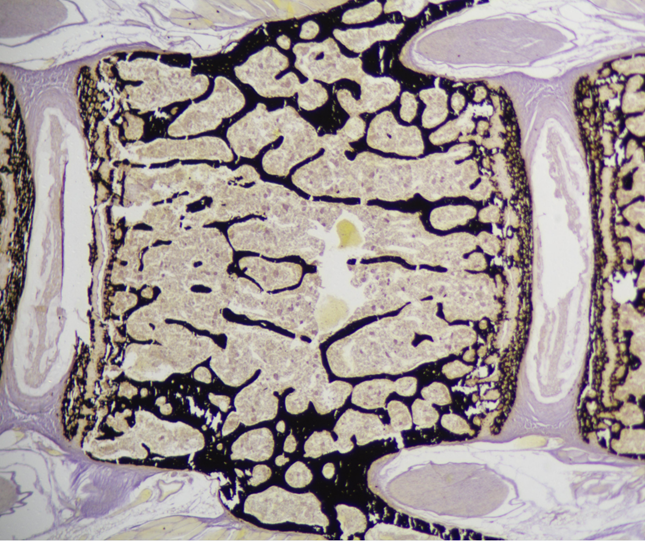

树脂包埋切片法是骨组织以及其他硬组织材料研究的最佳方法之一。无需脱钙,能够完整保留骨骼的成分,可用于骨形成及矿化沉积的分析,例如BFR,MAR等。我们采用甲基丙烯酸甲酯(MMA)树脂包埋法,可对骨组织及其他硬组织(种子,以及早中期牙齿等),进行切片(HistoCore Autocut, Leica)及分析(Osteomeasure 软件)。

样图: